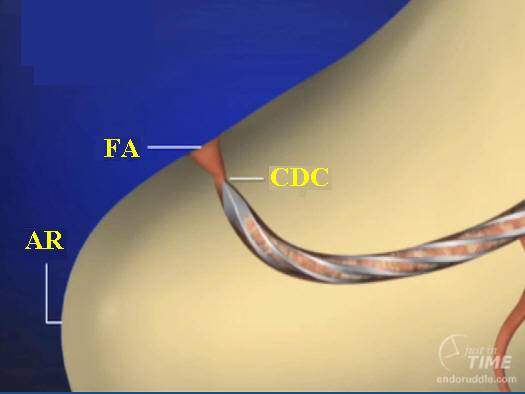

6-

Conductometría con RX:

consiste en determinar la longitud precisa entre el

CDC de cada

conducto y el borde incisal o la cara oclusal del diente en

tratamiento, considerando como longitud óptima 0,5 a 1mm. del ápice radiográfico

AR.

Pasos a

tener en cuenta

1.

Se

toma una radiografía inicial de diagnóstico

ortorradial, con el diente en el centro de la

placa, preferiblemente con técnica paralela. Se

mide la longitud de todo el diente desde el

borde incisal o cúspide oclusal hasta la porción

más apical del diente.

2.

Se

resta 1 mm. a dicha longitud (distancia

existente entre ligamento periodontal y el CDC,

no observable en la radiografía). Conocer la

longitud promedio del diente es de gran ayuda

para determinar la longitud aproximada de

trabajo.

Nota: Hoy en día la conductometría por medio de la radiología para

determinar la longitud de trabajo, ha sido

complementada para una mejor exactitud, por los localizadores electrónicos de

ápices, que tienen como objetivo llegar a límite cemento

dentina cemento (CDC)